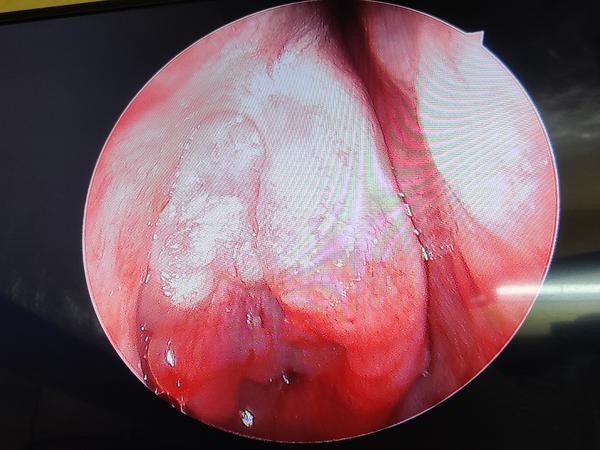

View DetailsEndoscopic medial maxillectomy

View DetailsFESS Surgery in Nagpur